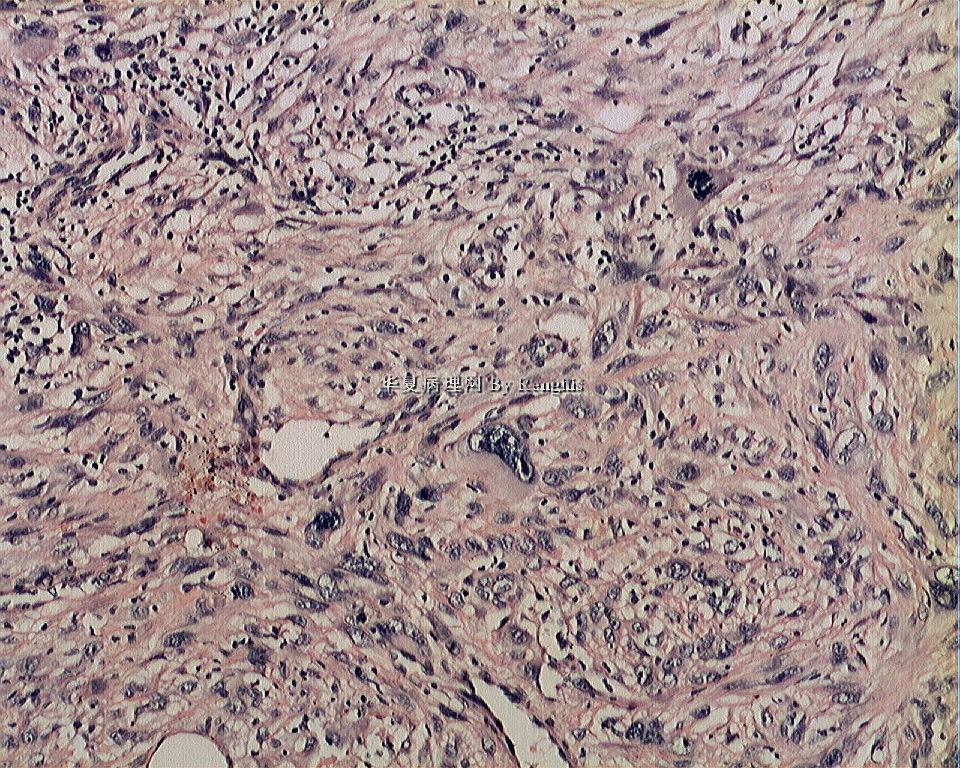

女,29岁,左大腿内侧肿物直径2.8cm,切面灰白、实性、质中,似有包膜。

本例就形态学而言不太符合纤维肉瘤,对于一个多形性和异型明显的肿瘤首先不考虑纤维肉瘤的诊断加上车辐状结构首先还是考虑纤维组织细胞肿瘤。

本人认同此例是一例比较典型的纤维肉瘤,瘤细胞程束状、鱼骨状及编织状排列,部分瘤细胞异型性明显,免疫组化vimentin阳性,SMA灶状弱阳性,desmin阴性,S100阴性,CK阴性,EMA阴性,余记不得了,明天看看再上传。